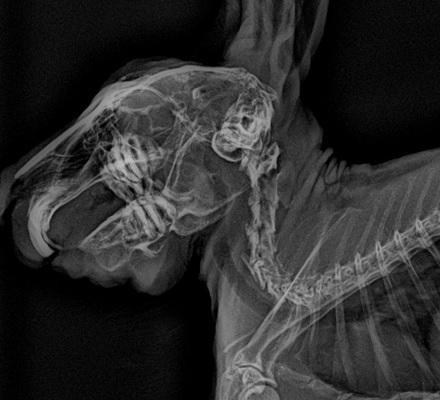

門牙感染、充滿膿液

牙根過長(食物太過多樣化、兔兔挑食誘發只食甜食,拒食硬草)

2. 影像檢查:X 光可評估腸道氣體、糞塊位置和牙齒結構;或需鎮靜。

• 牙科問題:在麻醉下修整牙齒,移除尖刺,或處理牙根膿腫。術後需服用止痛及抗生素。